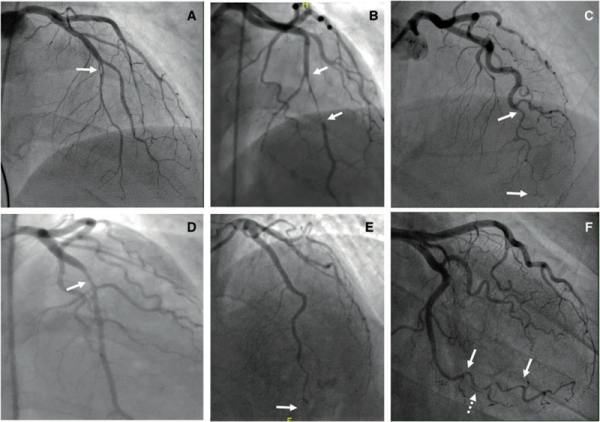

Figure 1A : Réseau coronaire gauche : incidence caudale

Figure 1B : Réseau coronaire gauche : incidence apicale (10/40)

Figure 1C : Réseau coronaire droit : incidence oblique gauche

Au vu de l’aspect angiographique, la dissection coronaire spontanée est le diagnostic le plus probable.

Cependant, le diagnostic de sténose serrée d’origine athéromateuse ou celui de spasme coronaire ne peuvent pas être formellement écartés. L’aspect angiographique n’est pas évocateur de thrombus (qui aurait eu une composante plus hétérogène).

Figure 2 : Coronarographie : réseau coronaire gauche - incidence apicale (10/40)

Les incidences caudales permettent de visualiser correctement le réseau latéral avec l’artère circonflexe et ses marginales. Les incidences crâniales permettent de bien dérouler l’IVA et ses branches de division (artères diagonales et septales).

La coronarographie met en évidence un réseau gauche dominant, non athéromateux, avec des artères plutôt « lisses », hormis sur l’incidence crâniale « 10°/40° » (pour 10° d’oblique antérieure droite et 40° de crânial) où l’on met en évidence une sténose d’allure significative de l’IVA distale, qui persiste après injection de dérivé nitré. Il existe une réduction de calibre homogène qui débute et qui se termine en regard de petites branches de bifurcation, avec un aspect dit de « phasme ». Le flux coronaire est préservé, TIMI 3. Il n’y a pas de thrombus visible sur cette coronarographie. Cet aspect évoque en premier lieu une dissection coronaire spontanée.

Figure 3A : Classification des dissections coronaires spontanées illustrées

Figure 3B : Classification angiographique des dissections coronaires spontanées. Type 1 (A), Type 2A (B), Type 2B (C), Type 3 (D), Type 4 (E), intermédiaire entre Type1/2 (F).

- Type 1 : image classique en double lumière linéaire avec l’identification d’un flap radio transparent, fréquemment associé à une rétention de produit de contraste dans la fausse lumière.

- Type 2 : réduction de calibre diffus. Le type 2A est délimité en amont et en aval de la lésion par des segments de calibre normal. Le type 2B est défini par la réduction de calibre s’étendant jusqu’à la partie terminale de l’artère coronaire.

- Type 3 : sténose focale ou tubulaire (< 20 mm en général), presque non distinguable à l’angiographie d’une sténose secondaire à une lésion athérosclérotique.

- Type 4 : occlusion complète de la lumière par le faux chenal compressif